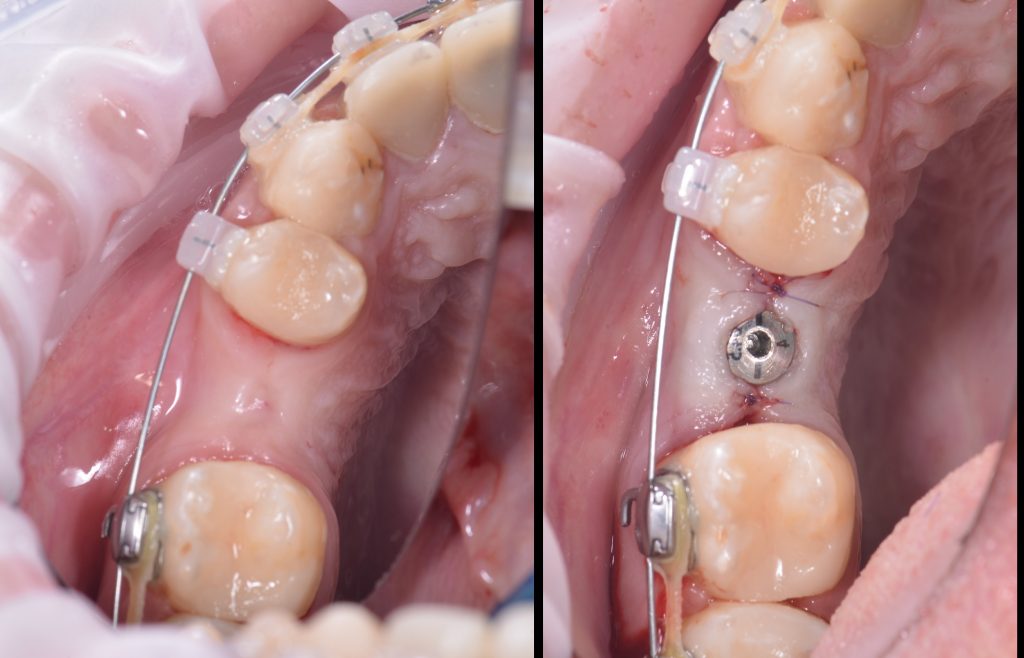

Based on these models, stereolithographic models were produced to plan the placement of the titanium mesh and ensure its accurate fit